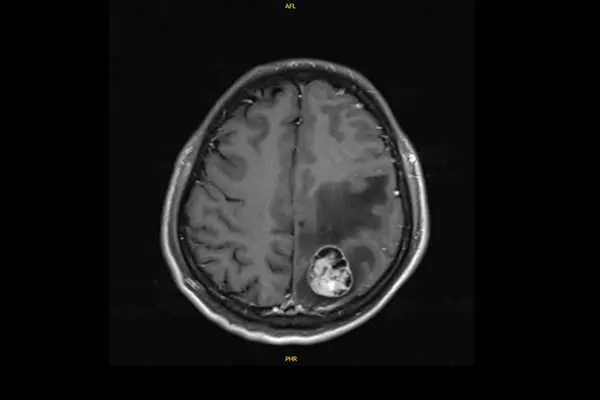

今年41歲的許先生,原從事文具業務,是家中主要經濟支柱;三年前(2022年)6月某日清晨,突然出現右側肢體無力與抽搐,倒地不起。家人驚慌之下緊急送至彰基急診。經電腦斷層及核磁共振檢查,醫師發現腦部有約3.1公分腫瘤,進一步追蹤又在右下肺發現4公分腫塊,確診為肺腺癌合併腦轉移。

儘管標靶藥物初期控制良好,許先生仍出現神經症狀。胸腔內科隨即啟動跨科整合照護,與神經外科孫立偉醫師合作完成腦部腫瘤手術,術後神經功能逐漸恢復。考量長期治療效果,林聖皓主任與胸腔外科再度召開跨科討論,由洪維亨醫師進行肺葉切除手術達成更徹底的控制;洪醫師指出,肺癌合併腦轉移的手術風險高,但彰基具備完整的影像導引與重症照護體系,使病人能安全完成手術。